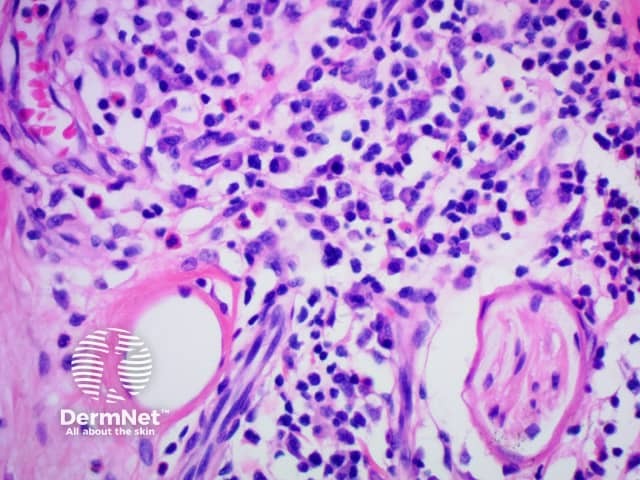

Generally, the minimum for making the diagnosis for most tissues is from 30 to 50 IgG4-positive cells per high power field. However, in some organs or tissues e.g kidney, only 10 IgG4-positive plasma cells per high power field may be sufficient.

Figure 5

The diagnostic criteria on histology proposed for skin disease are the following: